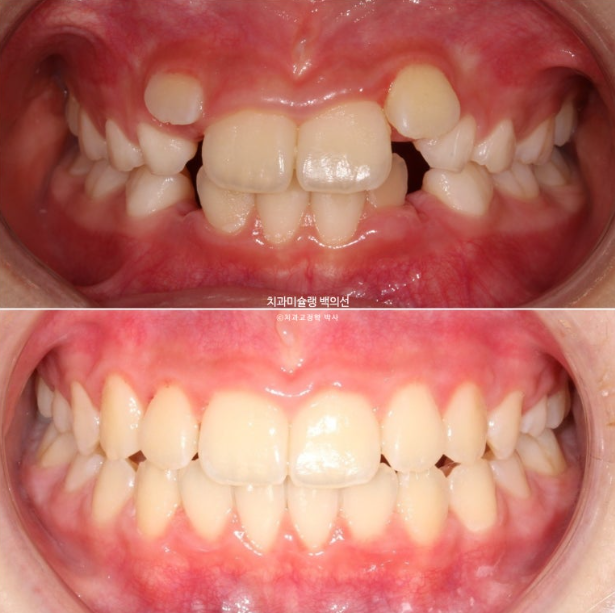

2년 전 교정치료를 위해 내원한 만 8세 어린이입니다.

이제 겨우 유치 앞니가 빠지고 영구치 앞니가 나오는 시기인데

앞니부터 심한 덧니로 내려오니 부모님이 놀라서 오셨습니다.

25년 6월 드디어 치료를 마무리 했습니다.

25.06

중심선은 잘 맞습니다.

아직 작은어금니들이 좀 더 내려와야 교합이 안정됩니다.

23.06~25.06

남아있는 유치는 없고 완전한 영구치열에 접어들었습니다.

나중에 2차교정을 안해도 될 정도가 되었습니다.